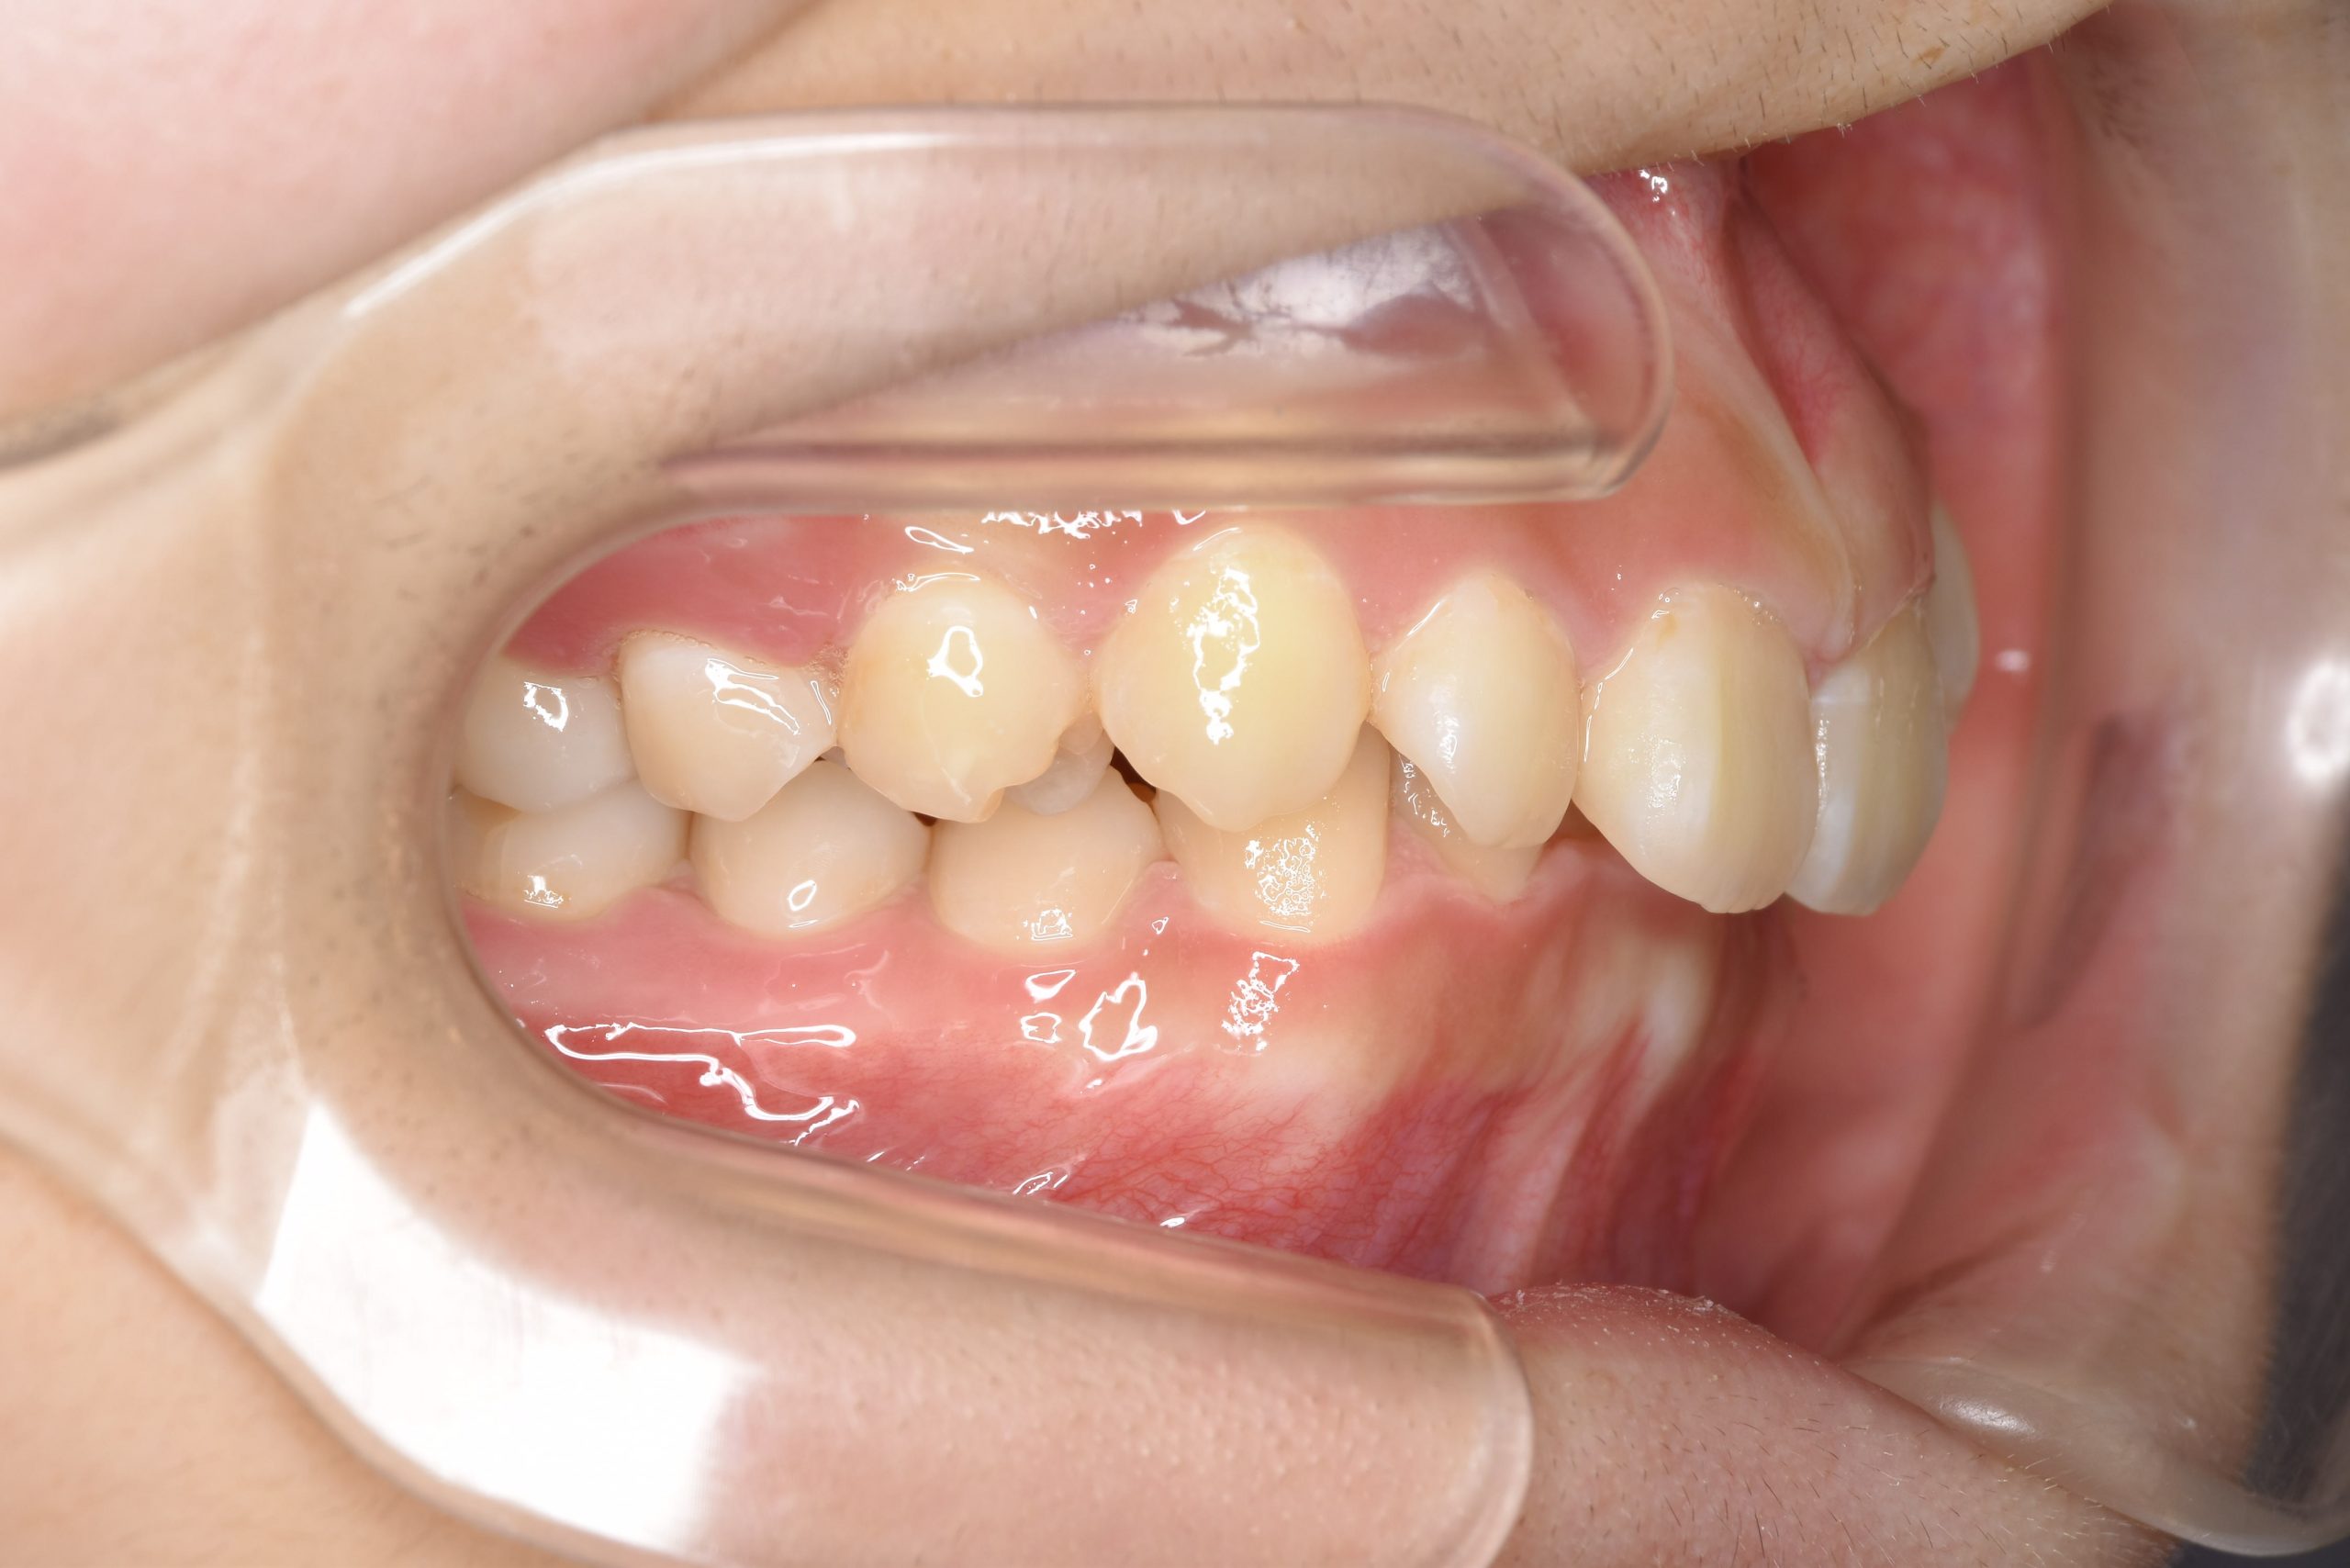

アフター

施術内容 MSEと下顎リンガルアーチを用いて上下顎骨を拡大した。

その後マルチブラケット装置を用いて非抜歯で歯牙を配列し、良好な咬合を獲得した。

治癒期間 3年7か月間